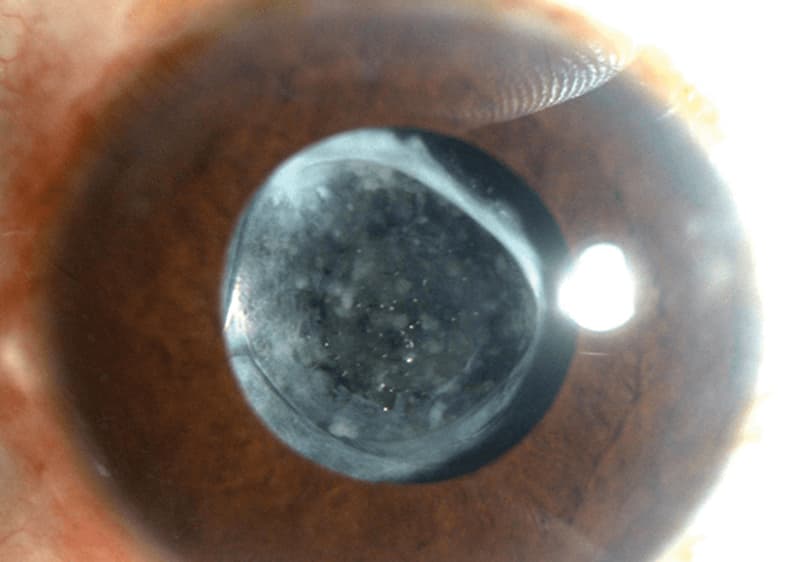

La capsulotomía con láser YAG es un procedimiento que abre la cápsula posterior opaca del cristalino después de una cirugía de cataratas. Según la Academia Americana de Oftalmología, es rápida y efectiva para restaurar la visión.

Para tratar opacidades de la cápsula posterior después de cirugía de cataratas.